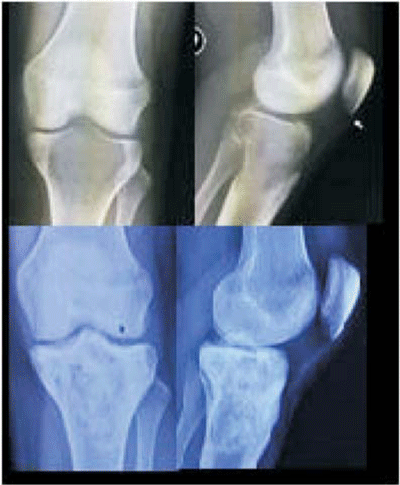

Paciente de 32 años, sexo femenino, antecedentes personales de fumadora. Comienza en el año 2014 con gonalgia izquierda que se interpreta de causa meniscal, sin respuesta al tratamiento indicado. Consulta nuevamente en el año 2015 por permanencia de la gonalgia, dificultad en la marcha, disminución del rango de movilidad y tumoración a nivel de cóndilo externo de fémur distal. Se realiza estudio imagenológico con Rx, TC y RNM donde se evidencia lesión lítica de cóndilo externo; la biopsia confirma el diagnóstico histopatológico de TOCG estadio III de Campanacci. En el momento del diagnóstico se plantea como tratamiento de elección la resección amplia y sustitución protésica o la amputación. Se inicia tratamiento con denosumab según protocolo planteado a paciente anterior. La paciente se presenta sin dolor al mes de iniciado el tratamiento. Se discontinúa el uso del anticuerpo a la quinta dosis, lográndose el efecto deseado (esclerosando los límites periféricos de la lesión). Del procedimiento se destaca resección intralesional, fresado rápido y cauterización de las paredes de la cavidad; reconstrucción con cemento y osteosíntesis (figura 2). A los cuatro meses del posoperatorio la paciente no presenta dolor, deambula con un bastón, mejoría franca de la amplitud de movimiento de la rodilla y la lesión clínica e imagenológicamente se considera controlada.

Figura 2: Arriba: lesión antes del tratamiento y evolución preoperatoria. Abajo: después de la cirugía planteda luego del tratamiento con denosumab.